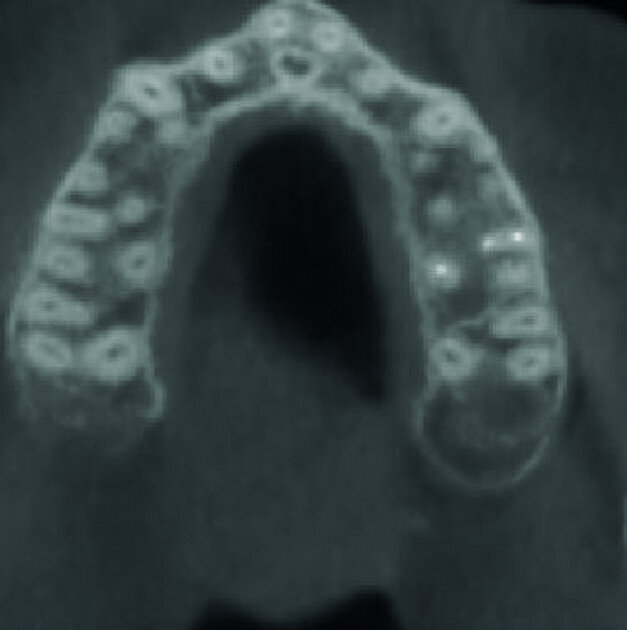

A patient was referred to the office with problems related to separated files. He was a pilot and was complaining of pus draining from his nose when flying. From the preoperative radiograph (Fig. 1), it was clear that there were two separated file fragments in the mesial canals and one cone passing beyond the apex in the palatal root. I requested an iCAT scan, and from this, the left sinus was clearly almost full with inflammatory fluid (Fig. 2) and the cone in the palatal canal was clearly emerging into the sinus. We could also see the two separated files in the two mesial canals clearly in the MPR view (Figs. 3 & 4), as well as another file entering the sinus and not attached to the canal (Fig. 5). We could see the file using different filters (Figs. 6–9), as well as the inflammation inside the sinus and the separated file. We additionally gained a better idea of the location of the cone protruding from the palatal canal into the sinus.

The treatment plan was to try to solve it with a conventional approach and if necessary to perform microsurgery to save the tooth. With the help of H-files, I managed to retrieve the cone from the palatal root, but the files inside the mesial root were impossible to bypass or even to reach with ultrasonic tips. I decided not to overdo it in order to avoid creating an additional problem, like perforating the canal, and decided to seal the canals (Fig. 10). A surgical approach was immediately taken for the mesial canals, cutting 3 mm of the mesial root using the Impact Air handpiece (SybronEndo), and this gave me a direct view of the Schneiderian membrane, where the third file was barely hanging (Figs. 11 & 12). I managed to delicate grab it and to remove it (Fig. 13). Figure 14 shows the postoperative situation, after performing retrograde preparation of the mesial canals.